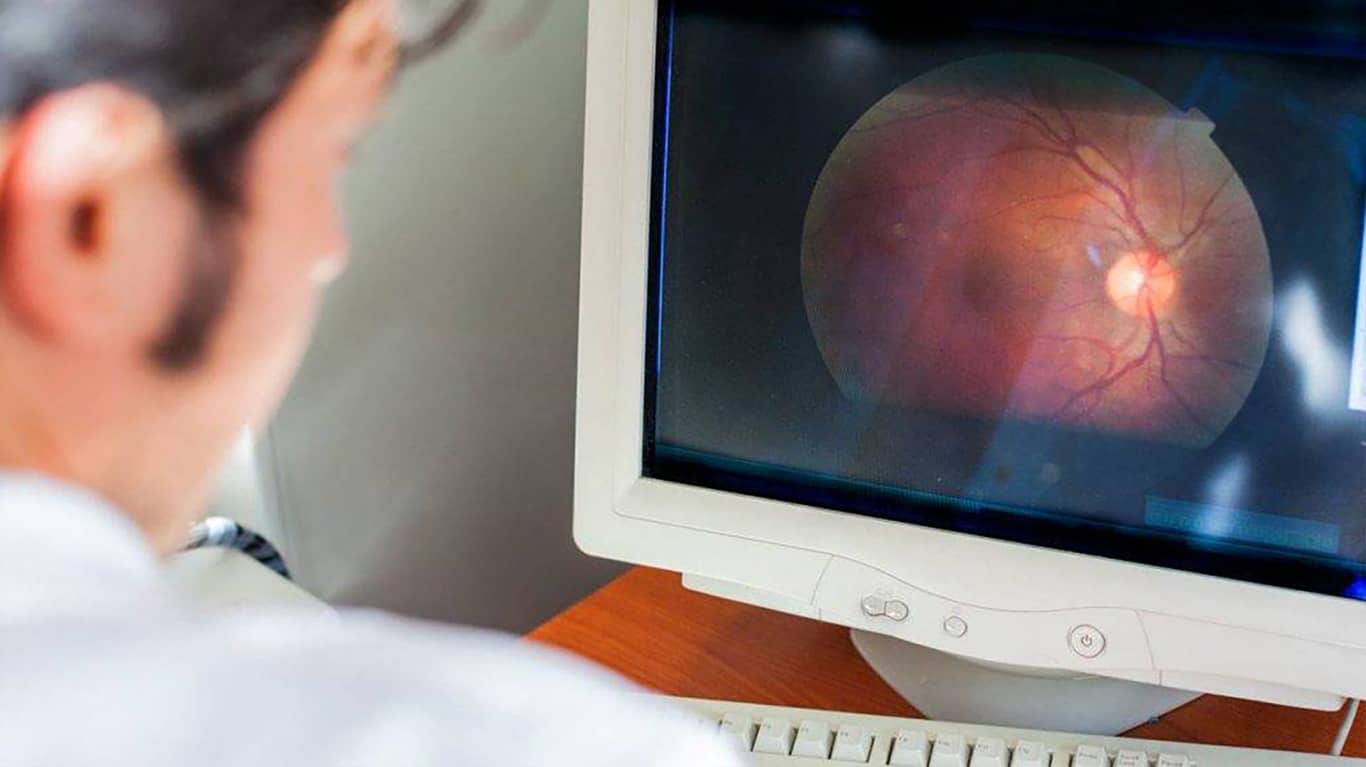

چشم پزشکان (چشم پزشکانی که درمان های پزشکی و جراحی برای بیماری های چشمی انجام می دهند) و بینایی سنج ها معمولاً فشار خون بالای چشمی را در طول معاینات معمول چشم تشخیص می دهند. آن ها می توانند پس از پرسیدن سابقه پزشکی بیمار، انجام معاینه و ارائه آزمایش های تشخیصی، وجود این بیماری را تأیید کنند. هنگام صحبت با چشم پزشک در مورد سلامت کلی خود، حتماً به پزشک خود بگویید که آیا دیابت یا فشار خون بالا دارید یا خیر. همچنین مهم است که جزئیات مربوط به هرگونه سابقه خانوادگی گلوکوم یا فشار خون بالای چشمی را به اشتراک بگذارید. اگر جراحی چشم، تزریق چشم یا آسیب چشمی در گذشته داشته اید، به پزشک اطلاع دهید. چشم پزشکان نمی توانند فقط با نگاه کردن به چشمان بیمار تشخیص دهند که او فشار خون بالای چشمی دارد. آن ها می توانند این بیماری را در طول یک معاینه جامع چشم، که شامل آزمایش ها و ارزیابی های مختلفی برای بررسی سلامت کلی چشم بیمار است، تشخیص دهند.

تونومتری: پزشک شما فشار چشم شما را با استفاده از روشی به نام تونومتری اندازهگیری می کند. انواع مختلفی از تونومتری وجود دارد. در دقیق ترین نوع، که به عنوان تونومتری آپلاناسیون شناخته می شود، پزشک چشم بیمار را با قطره های چشمی بی حس میکند و به طور موقت چشم ها را با استفاده از رنگی که ممکن است از طریق قطره های چشمی یا نوار کاغذی با رنگ نارنجی روی آن داده شود، رنگ آمیزی می کند. در حالی که چانه بیمار روی یک لامپ شکافی قرار دارد، پزشک تونومتر آپلاناسیون را به سمت چشم شما هدایت می کند تا زمانی که به قرنیه برخورد کند. این دستگاه میزان فشار لازم برای صاف کردن بخشی از قرنیه را اندازه گیری می کند که به پزشک اجازه می دهد فشار داخل چشم را تعیین کند. روش دیگری که به عنوان تونومتری غیرتماسی شناخته می شود شامل استفاده از یک دستگاه مخصوص برای هدایت یک پاف هوا به چشم برای صاف کردن قسمت مرکزی قرنیه است. دستگاه به طور خودکار فشار داخل چشم را محاسبه می کند. تونومتری غیرتماسی نیازی به قطره های بی حسی ندارد. فشار داخل چشم بین ۱۲ میلی متر جیوه و ۲۱ میلی متر جیوه طبیعی در نظر گرفته می شود. اندازه گیری های بالاتر از ۲۱ میلی متر جیوه در دو نوبت جداگانه، فشار خون بالای چشمی در نظر گرفته می شود.

گونیسکوپی: اگر فشار داخل چشم بیمار بالا باشد یا اگر پزشک مشکوک به وجود سایر مشکلات چشمی در بیمار باشد، ممکن است آزمایش های اضافی از جمله گونیسکوپی لازم باشد. این آزمایش در حالی انجام می شود که بیمار چانه و پیشانی خود را روی یک لامپ شکافی قرار می دهد. پزشک یک لنز تماسی مخصوص را روی سطح چشم بیمار قرار می دهد. این لنز تماسی دارای آینه هایی است. نوری که از طریق لامپ شکافی تابیده می شود، به زاویه تخلیه، جایی که مایع معمولاً از محل تقاطع عنبیه و صلبیه (قسمت سفید چشم) از چشم خارج می شود، هدایت می شود. پزشکان می توانند ببینند که آیا مایع به طور طبیعی جریان دارد یا انسدادی وجود دارد. در صورت وجود انسداد، پزشکان معمولاً می توانند علت را شناسایی کنند. آزمایش های دیگری نیز ممکن است برای تعیین اینکه آیا کاهش بینایی یا هرگونه آسیبی به عصب بینایی وجود دارد یا خیر، یا برای اندازه گیری ضخامت قرنیه انجام شود که ممکن است بر خطر ابتلا به گلوکوم در بیمار تأثیر بگذارد. اگر آزمایش ها کاهش بینایی یا آسیب به عصب بینایی را نشان دهند، پزشک گلوکوم را در بیمار تشخیص می دهد.